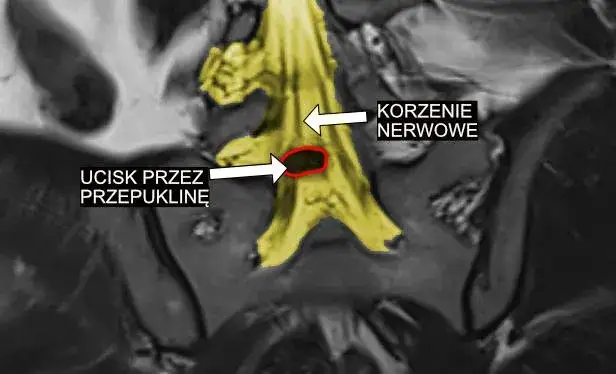

Za większością dolegliwości związanych z uciskiem na nerwy w Polsce stoi choroba zwyrodnieniowa kręgosłupa. Kluczową rolę odgrywa tutaj dyskopatia, czyli schorzenie krążka międzykręgowego, objawiające się jako jego przepuklina lub wypuklina, która może naciskać na korzenie nerwowe. Równie częste są zmiany wytwórcze, czyli tzw. osteofity, zwane potocznie "dziobami", które powstają na trzonach kręgów i mogą zwężać otwory międzykręgowe, przez które wychodzą nerwy. Dodatkowo, stenoza kanału kręgowego, czyli jego zwężenie, może prowadzić do ucisku nie tylko na rdzeń kręgowy, ale także na wychodzące z niego korzenie nerwowe.

Rezonans magnetyczny (MRI): dlaczego to "złoty standard" w obrazowaniu ucisku?

Kiedy potrzebujemy precyzyjnie ocenić stan tkanek miękkich, takich jak krążki międzykręgowe, korzenie nerwowe czy rdzeń kręgowy, rezonans magnetyczny (MRI) jest badaniem z wyboru. Jest on uznawany za "złoty standard" w diagnostyce schorzeń kręgosłupa i ucisku na nerwy, ponieważ pozwala na uzyskanie bardzo szczegółowych obrazów w różnych płaszczyznach, uwidaczniając nawet niewielkie zmiany. Choć tomografia komputerowa (CT) może być pomocna w ocenie struktur kostnych, a badanie RTG stanowi często pierwszy krok diagnostyczny, to właśnie MRI dostarcza najwięcej informacji o przyczynach ucisku na korzenie nerwowe.